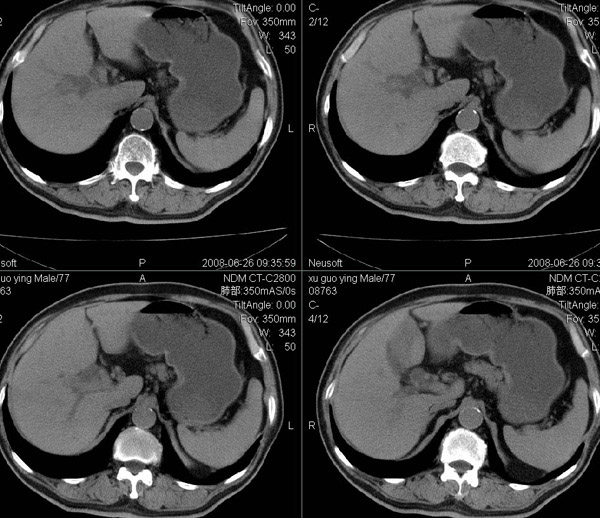

以下是引用狙击手在2008-6-26 20:16:00的发言:[br]上腹部除了胆囊大一点,其余未见明显异常,肺尖部见纤维条索样影,左肺下叶见空洞样占位,壁较厚,临近胸膜见牵拉,周围未见卫星灶,考虑:1:左下肺周围性肺癌;2:肺尖部陈旧性结合灶。

以下是引用liuqiang在2008-6-26 21:11:00的发言:[br]上腹部除了胆囊大一点,其余未见明显异常,肺尖部见纤维条索样影,左肺下叶见空洞样占位,壁较厚,临近胸膜见牵拉,周围未见卫星灶,考虑:1:左下肺周围性肺癌;2:肺尖部陈旧性j结核灶。